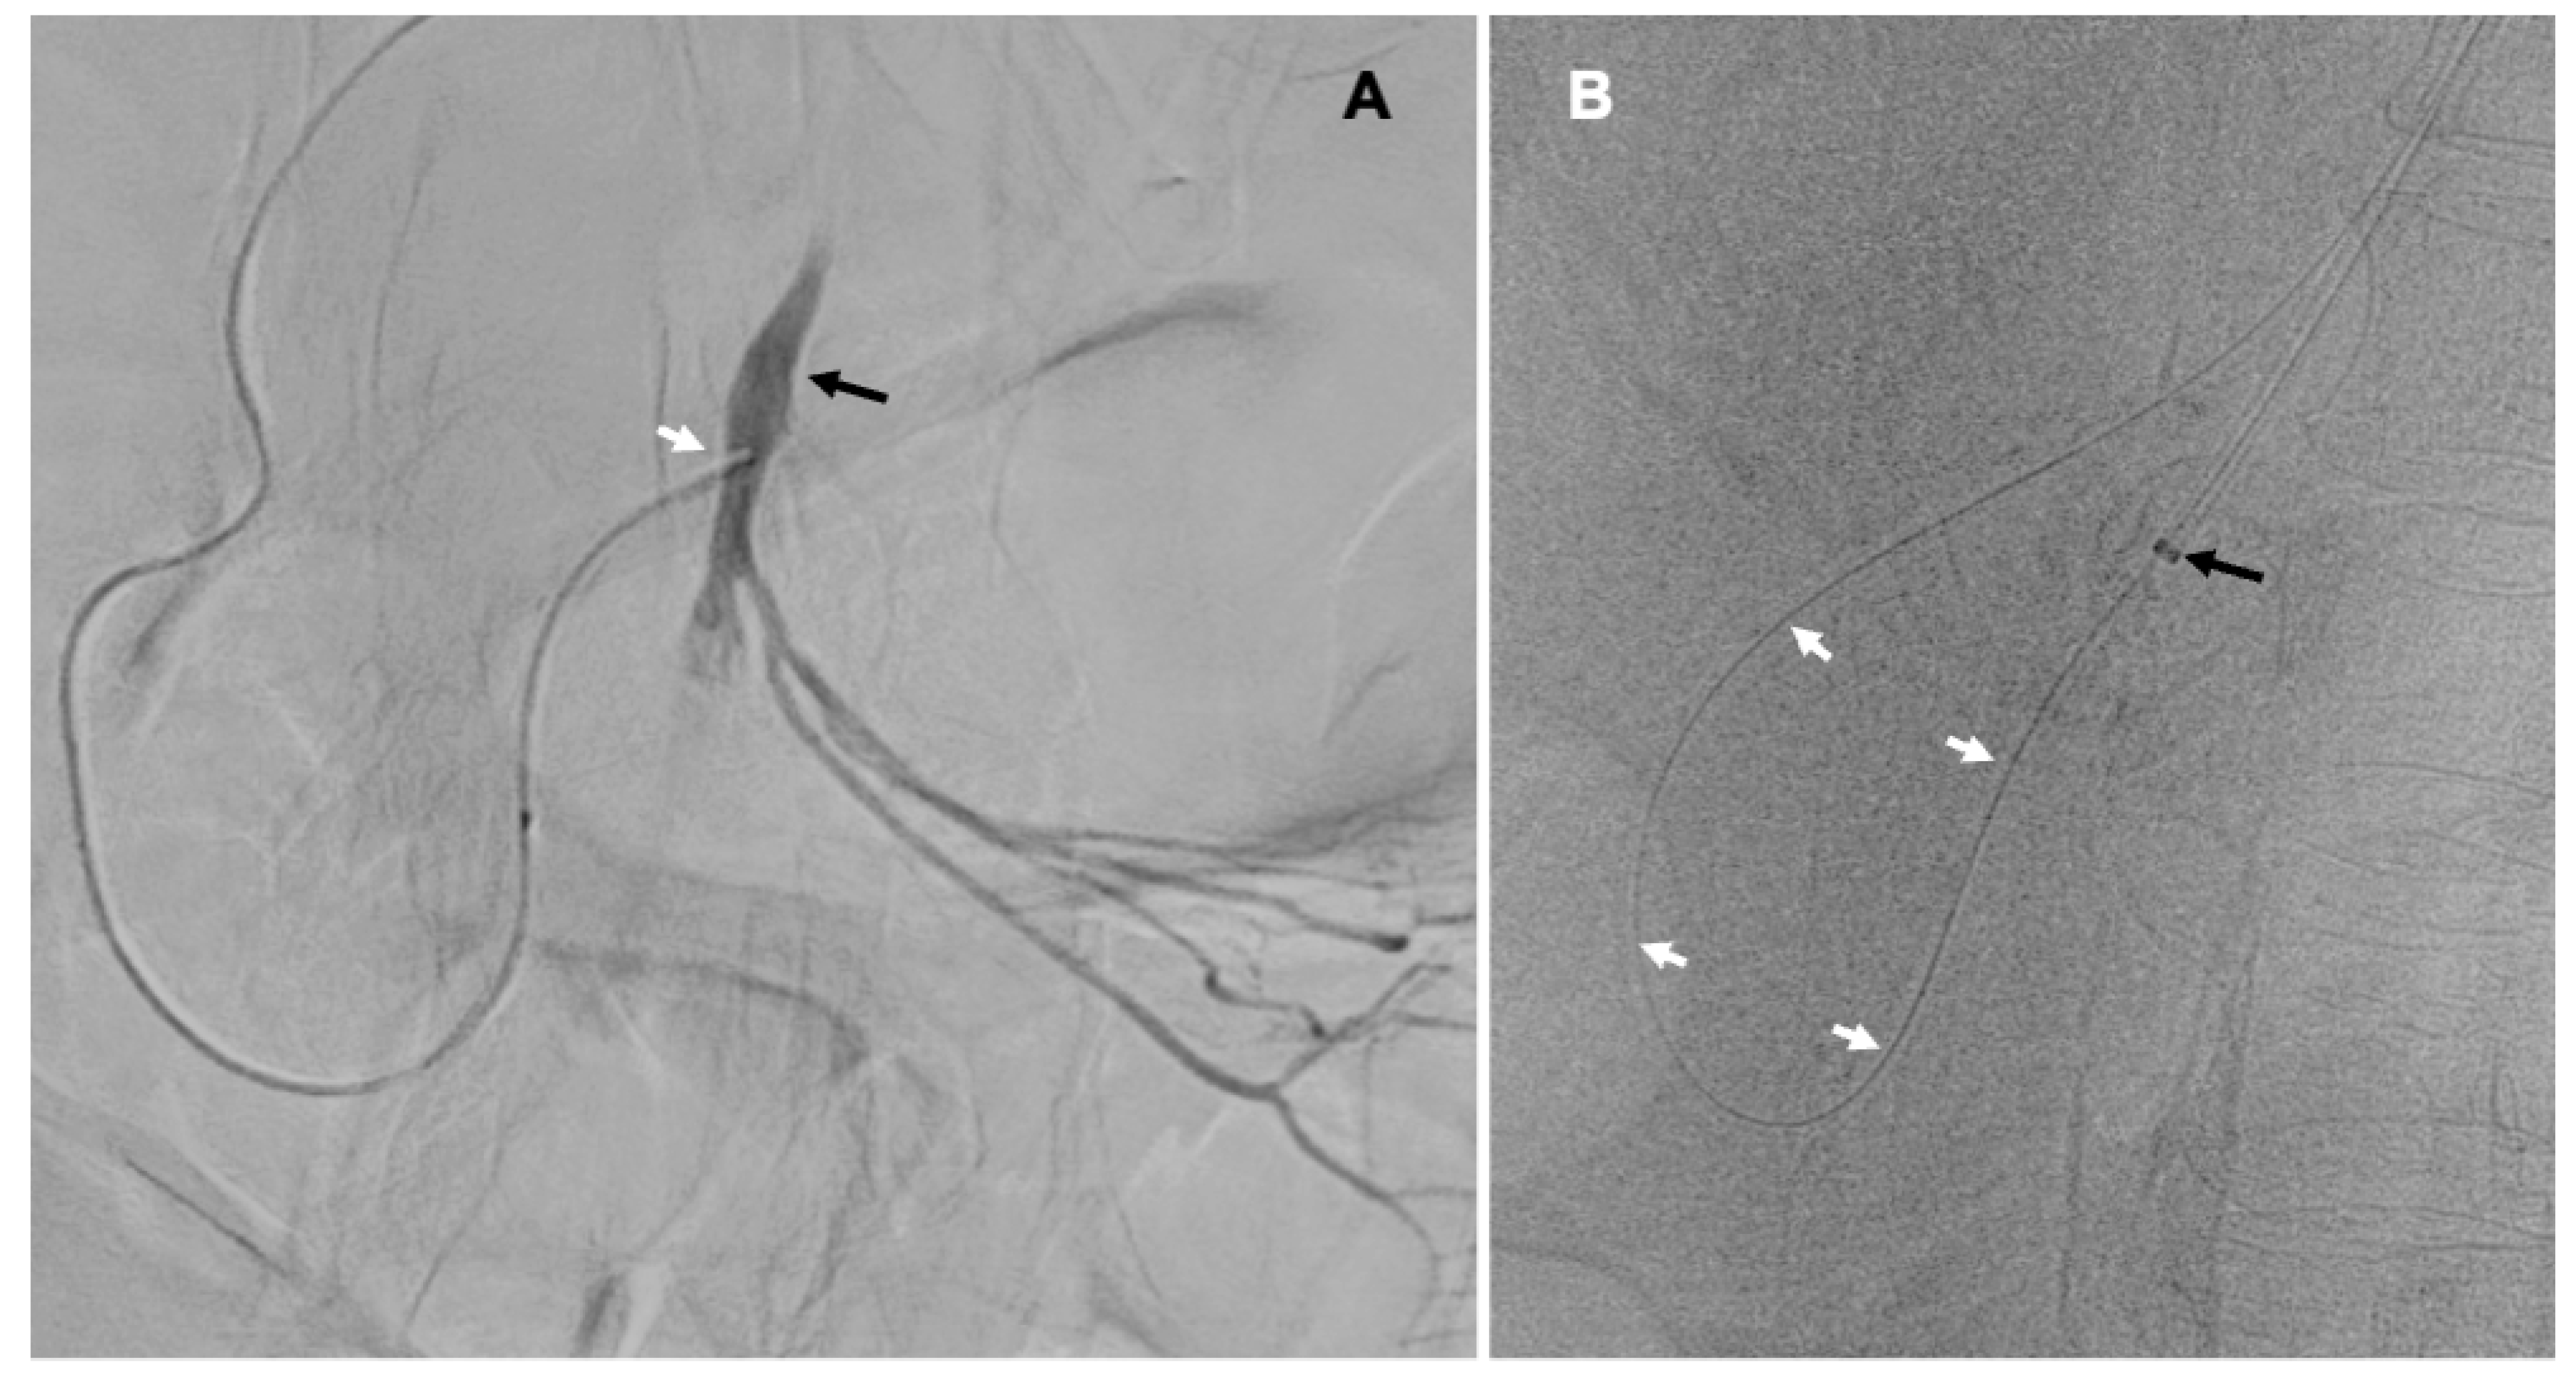

Here, we present the case of percutaneous retrograde recanalization of an occluded SMA in the patient presenting with ABI. An 82-year-old female patient developed progressing abdominal symptoms during hospital stay after thrombarterectomy of the femoral artery, which was performed for the treatment of critical lower limb ischemia. CT angiography revealed calcified plaques in the SMA, located 3 mm distally from the aorta (Figure 1A). This lesion completely occluded proximal part the SMA. This examination also demonstrated patent celiac trunk, wide common hepatic artery (CHA), and patent, although narrow, gastroduodenal artery (GDA). Distal branches of the SMA were not visible. The overall clinical picture suggested thrombosis of the SMA resulting in bowel ischemia.

Since the patient, in addition to abdominal symptoms, presented with heart failure and was hemodynamically very unstable, surgical exploratory laparotomy was not possible. Therefore, the decision upon a life-saving endovascular intervention has been made. Catheter angiography of the abdominal visceral arteries, which was performed from the left brachial access, did not show the SMA. When the catheter was advanced to the CHA, proximal part of the SMA was revealed. This artery received inflow though the GDA. Also, several proximal jejunal branches were shown, while other branches of the SMA were not visible (Figure 1B). Considering the fact that the origin of SMA was not visible, we decided to recanalyze this artery in a retrograde manner, via the branches of the celiac trunk.

Figure 1. A – CT angiography of the aorta (X) and visceral arteries (sagittal projection): a highly calcified plaque 3 mm from the aorta, occluding proximal segment of the superior mesenteric artery (black arrow); B – Catheter angiography of the celiac trunk – common hepatic artery (asterisk) and gastroduodenal artery (white arrows) and retrograde inflow to the proximally occluded superior mesenteric artery (black arrow) and no inflow to the distal part of superior mesenteric artery (X).

Figure 2. A – Microcatheter (white arrow) advanced to the superior mesenteric artery (black arrow) through the gastroduodenal and pancreaticoduodenal arteries; B – Guidewire (white arrows) navigated in a retrograde manner cross the lesion to the aorta caught to the introducer sheath (black arrow).